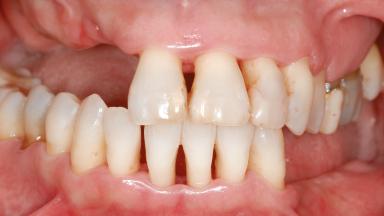

Shell Technique for Horizontal and Vertical Maxillary Bone Augmentation in a Partially Edentulous Patient with Aggressive Periodontal Disease

A 46-year-old woman was referred for treatment whose main complaints were mobility of her fixed partial dentures (right maxilla and left mandible) and periodontal bleeding during function. She also reported having taken systemic antibiotics to treat recurrent swelling in the area of the upper left molars. The patient had not seen a dentist for at least 2 years. She did not smoke and had no history of major systemic disease other than two minor orthopedic procedures some years back. The first-visit examination revealed poor plaque control, tooth mobility, periodontal disease, and a residual dentition widely associated with deep periodontal pockets.